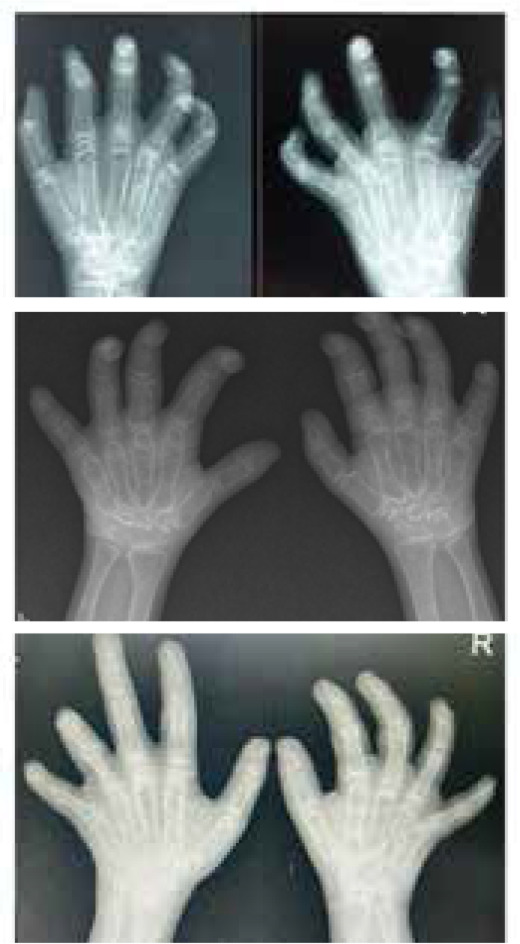

Multicentric Osteolysis Nodulosis and Arthropathy (MONA) is a rare skeletal disorder driven by mutations in the MMP2 gene, leading to bone and joint degradation. This case series presents three unique MONA cases, highlighting clinical, radiological, and genetic aspects. These insights shed light on the complexities of MONA, aiding early diagnosis and multidisciplinary management. Case 1 is a 13-year-old male, born to consanguineous parents, presented with a 5-year history of progressive joint deformities, pain, and difficulty walking. Initially diagnosed as juvenile idiopathic arthritis (JIA), despite treatment, his symptoms persisted. Examination revealed multiple clinical findings, including joint contractures and nodules. Genetic analysis identified a pathogenic variant in the MMP2 gene, confirming MONA. Case 2 and Case 3 were two siblings, aged 12 and 17 years respectively, who presented progressive joint contractures in their hands and feet since early childhood. Clinical examinations revealed contractures and subcutaneous nodules. Genetic analysis confirmed MONA with a shared homozygous pathogenic MMP2 variant, emphasising the genetic basis of this rare disorder.